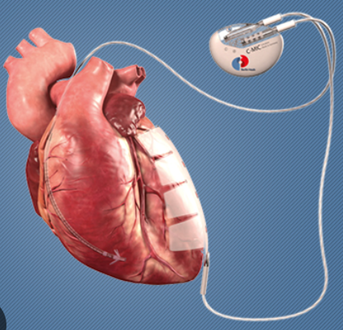

U sklopu međunarodnog projekta u Kliničkom centru Univerziteta u Sarajevu 58 godišnjem pacijentu ugrađen je uređaj za mikrostrujnu terapiju srca (Cardiac Microcurrent Therapy System C-MIC-II). Ovo je prvi put u historiji KCUS da je urađena ugradnja ovakvog uređaja.

Uloga ovog aparata je da kontinuiranom mikrostrujom određene frekvencije, poveća srčanu snagu i dovede do poboljšanja srčane funkcije.

ilustracija C-MIC-II uređaja radiografski prikaz C-MIC-II uređaja izvor – KCUS